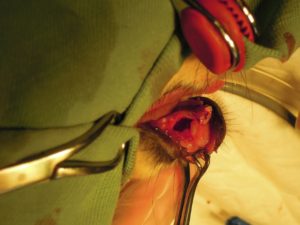

4.乳犬歯を抜歯して、歯肉を切除すると、永久犬歯が見えてきました。

5.周囲の骨を削り、犬歯を抜くスペースを作り

6.犬歯を抜歯してから、周囲の組織を切除して

7.大きな空洞が出来たので

8.骨補充剤を入れてから縫合しました。